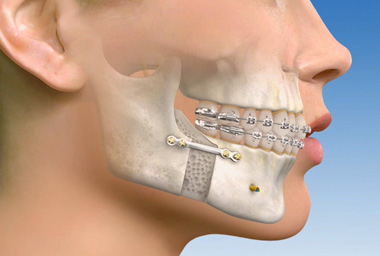

Ortodontiyle dişlerin yeniden konumlandırılması mümkün olduğu gibi ortognatik cerrahi ile de büyüme gelişimlerini tamamlamış erişkin hastalarda ki çene uyumsuzlukları düzeltilebilmekte, çiğneme, konuşma, soluk alma fonksiyonları iyileştirildiği gibi yüz görünümü de güzelleştirilebilmektedir.

Cerrahi öncesi 6-18 ay süreyle orthodontik hazırlık aşaması gerekmektedir. Bu aşamada dişlerinizin daha da kötüleştiğini düşünebilirsiniz fakat dişlerinizin konumları çenelerinizin ameliyat sonrasındaki konumlarına göre şekillenmektedir. Cerrahi sonrası çeneleriniz uygun konumlarına getirildiğinde dişlerinizin muntazam ilişkide olduklarını göreceksiniz.

Cerrahi işlem hastane ortamında, genel anestezi altında, çene cerrahisi uzmanı ve ekibi tarafından gerçekleştirilmekte ve gereken işlemin tipine bağlı olarak birkaç saat sürebilmektedir. İşlem sonrası 2 hafta içinde okul ya da işinize dönebilirsiniz. İşlemden sonra gereken iyileşme süresi sonunda (yaklaşık 4-8 hafta), ortodontistiniz kapanış ilişkinizi mükemmelleştirmek için ortodontik tedavinize devam edecektir. Çoğu vakada, braketleriniz cerrahi sonrası 6-12 ay içinde çıkartılmaktadır.